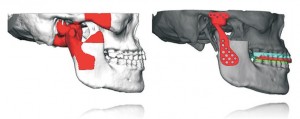

Hoje, o doutor explica que basta realizar, no paciente, uma tomografia tridimensional de sua face. “Depois, inserir no software que foi criado para o planejamento virtual calculando todas as medidas e desenhando o que o paciente necessita . Eu consigo operar o paciente diretamente na tela e criar os guias para o intra-operatório”, completa.

Após a análise tomográfica e a cirurgia virtual conseguimos avaliar qual a melhor oclusão e relação das bases ósseas. O método virtual é ainda mais eficaz para casos de assimetrias da face, harmonizando as discrepâncias de deformidades dento-faciais.

Esse tipo de tecnologia é utilizada por poucos profissionais, ela melhora a precisão do planejamento, dos resultados cirúrgicos e diminui o tempo da cirurgia e dos riscos do paciente. “Vou colocar o paciente em uma cirurgia onde saberei exatamente o que foi feito no computador, e que será repetido na face dele”, finaliza dr. Leonard.